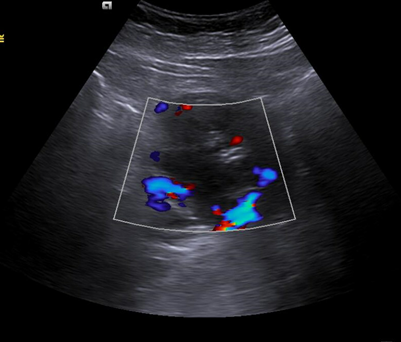

Riñón derecho 9,9 cm con morfología y ecogenicidad conservada. Presenta hidronefrosis grado III. No se identifica causa obstructiva.

Se remite a la paciente a Urgencias donde fue dada de alta con diagnóstico de CRU y tratamiento con Fosfomicina. Consultó al día siguiente, persistiendo el dolor y febrícula, remitiéndose de nuevo a Urgencias. Solicitan estudio de imagen con ecografía y ante los hallazgos se amplió el estudio a TC simple de abdomen: Hidronefrosis grado III con líquido perirrenal sugestivo de rotura de fórnix. Nefrolitiasis puntiformes en ambos cálices inferiores. Sin clara causa obstructiva objetivable. Se contactó con Urología de guardia quien propuso tratamiento ambulatorio con seguimiento posterior y colocación de nefrostomía programas y pielografía para estudio de probable estenosis de unión pieloureteral. Actualmente la paciente permanece en seguimiento por urología.